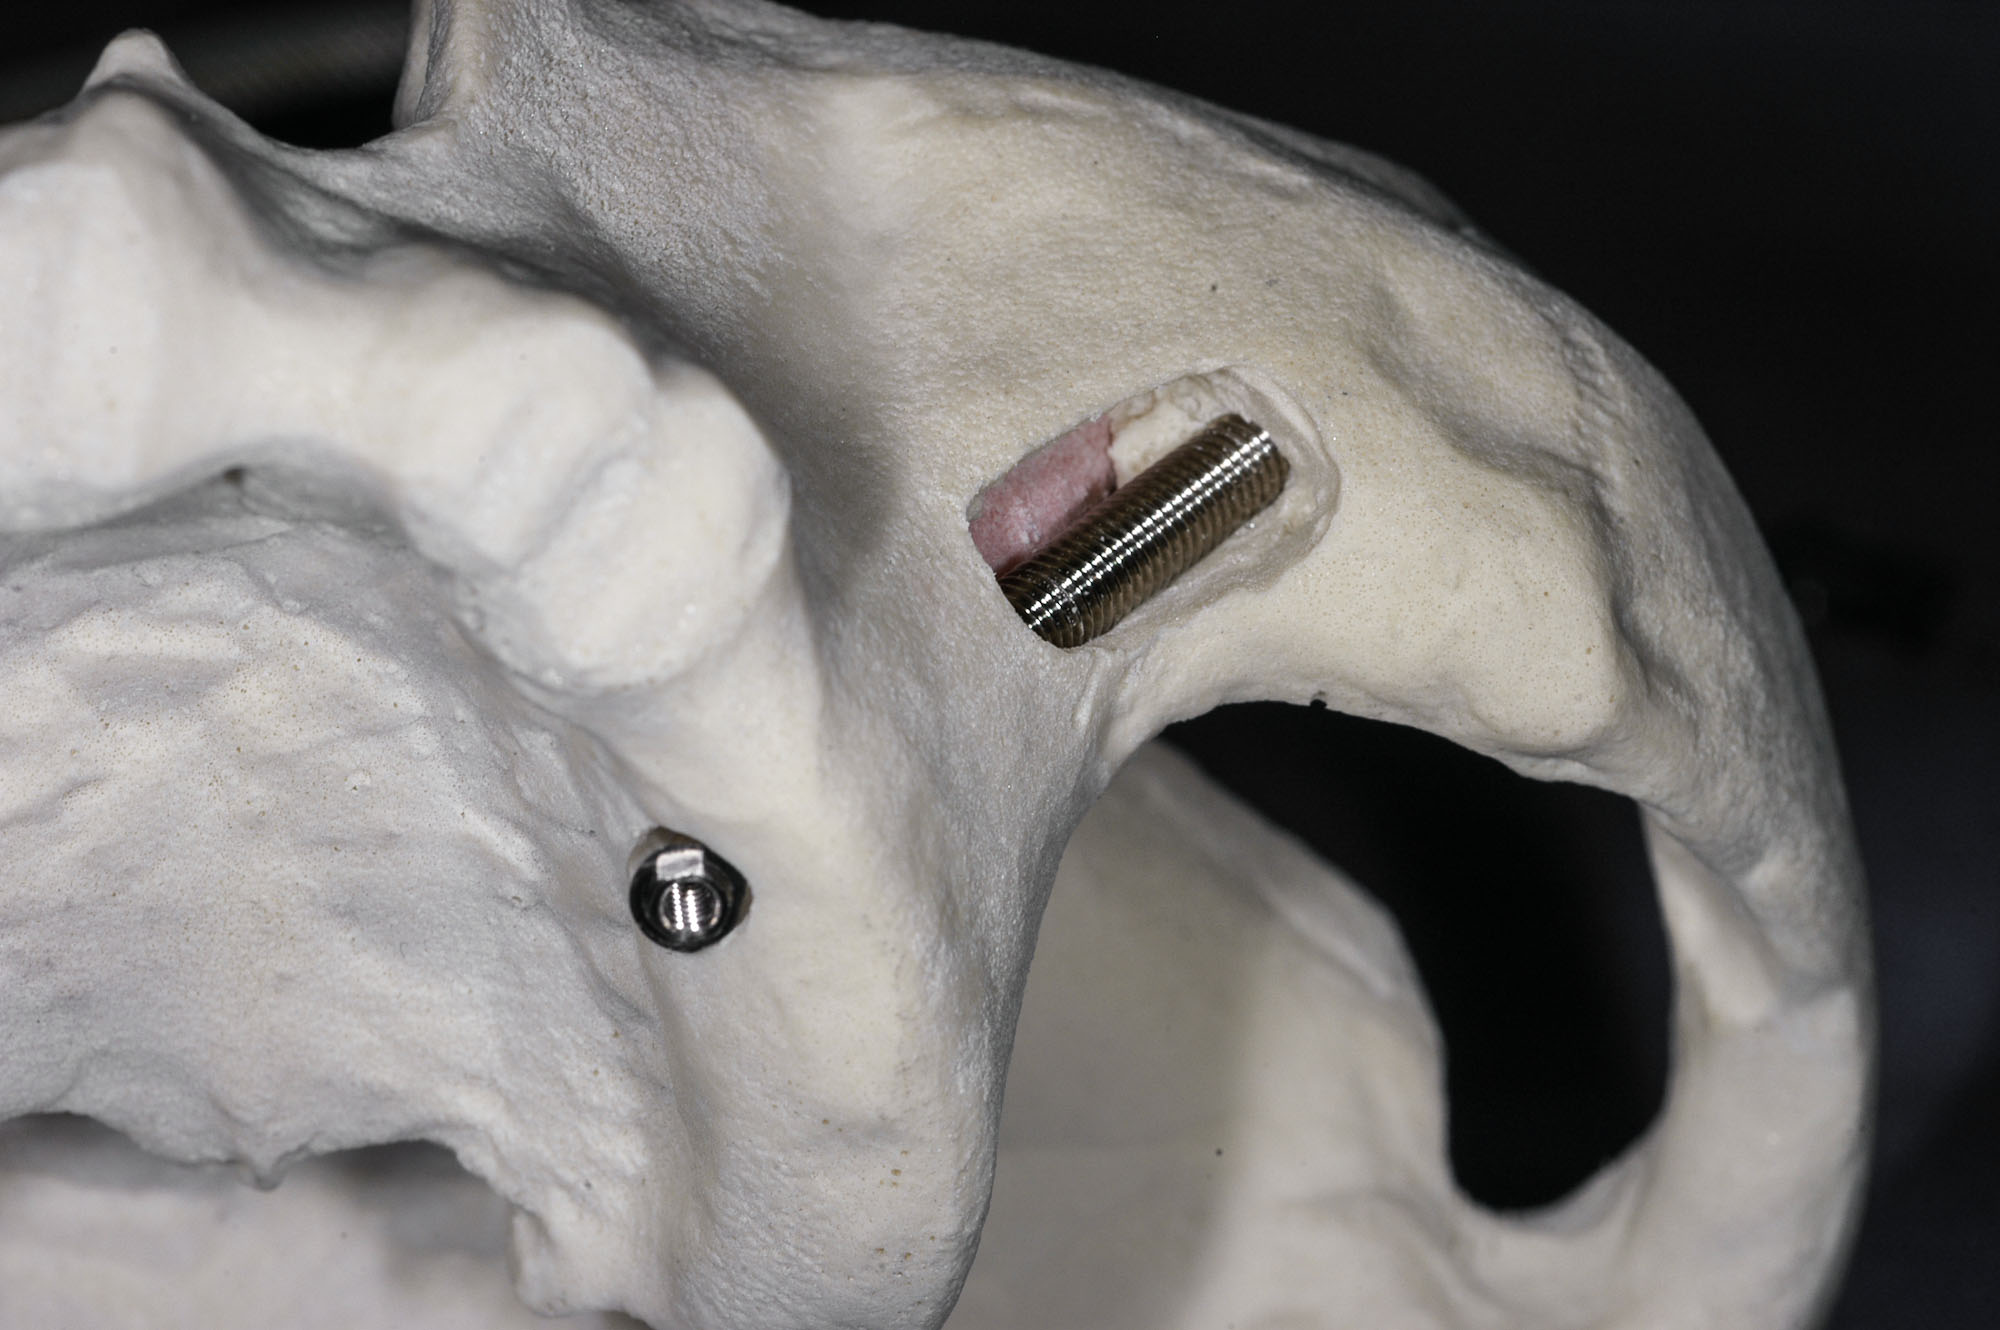

Są dużo dłuższe od typowych implantów i występują w długościach od 30 do 52,5 mm, aby w sytuacji braku kości w strefie części zębodołowej mogły dotrzeć i być mocno ustabilizowane w trzonie kości jarzmowej, znajdującej się w odległości kilku centymetrów od pozycji zębów.

Klasyczny implant Zygoma ma zróżnicowaną szerokość trzonu: 4,5 mm – 1/3 górnej i 4 mm – 2/3 dolnej, która uwzględnia optymalne jego mocowanie zarówno w zanikłej kości szczęki u dołu, jak i mocnej strukturze kości jarzmowej u góry, która jest w tych przypadkach podstawą w stabilizacji implantu. Dzięki jej budowie ta unikalna koncepcja lecznicza daje podstawy natychmiastowej odbudowy protetycznej uzębienia oraz stabilnych i długoterminowych efektów leczenia.

Istotna różnica w budowie w stosunku do tradycyjnych implantów to kąt główki, który wynosi 45° oraz 0°.

Koncepcja 45° wynika ze skośnej pozycji implantu mocowanego w zatoce szczękowej i trzonie kości jarzmowej, tak aby uprościć i zoptymalizować rozwiązania protetyczne.

Koncepcja 0° uwzględnia uproszczenie chirurgicznej części procedury, natomiast protetyczna część optymalizowana jest dzięki użyciu specjalnych łączników kątowych MultiUnit – jak w technice All-on-4.

Występują w dwóch wariantach różniących się rodzajem powierzchni. Starsze maja powierzchnię polerowaną maszynowo, nowsze pokryte są strukturą aktywną TiUnite, poprawiającą jakość i tempo osteointegracji.

Jest dłuższy od tradycyjnego implantu zębowego – występuje w długościach od 3,5 do 5,5 cm. Oryginalny ma kształt długiej zwężającej się śruby, natomiast jego szyjka wraz z platformą może być przedłużeniem jego osi lub stanowić kąt 45 stopni.